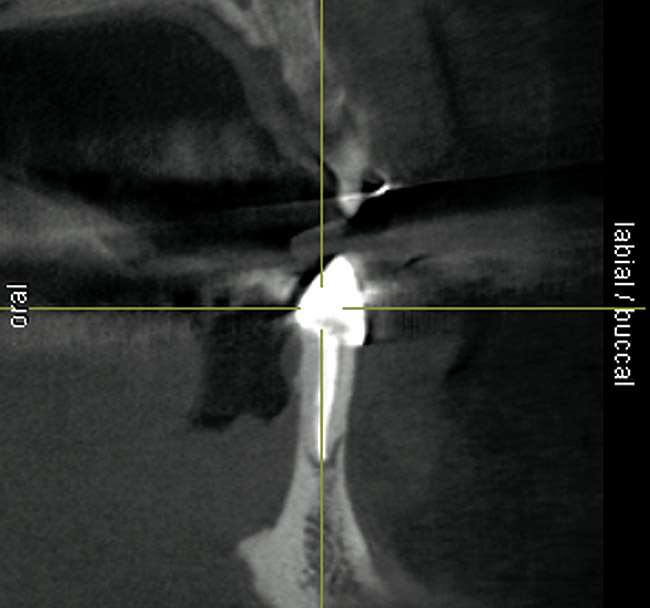

Figure 19  Scanning appliance worn by the patient for CT scan (Fig 19). Fabrication of a surgical template for flapless, computer-guided implant placement would be based on digital information obtained from the scan. Fig 20 demonstrates the cross-sectional view of the No. 8 position. Planning software demonstrated adequate 3-D volume for implant placement in this regenerated area where rhBMP-2/ACS and mesh were combined.

Figure 19

Figure 20  Scanning appliance worn by the patient for CT scan (Fig 19). Fabrication of a surgical template for flapless, computer-guided implant placement would be based on digital information obtained from the scan. Fig 20 demonstrates the cross-sectional view of the No. 8 position. Planning software demonstrated adequate 3-D volume for implant placement in this regenerated area where rhBMP-2/ACS and mesh were combined

Figure 20